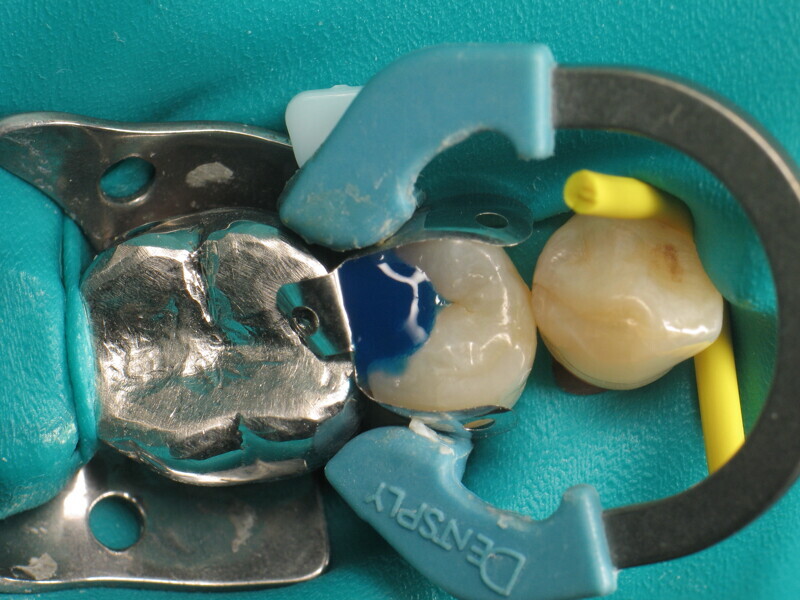

Le cas clinique décrit dans cet article porte sur une cavité de classe II sur une prémolaire (45) qui sera restaurée à l’aide d’un composite thermovisqueux (Fig. 1). La dent est isolée avec une digue en latex (Fig. 2). La cavité de classe II est ensuite nettoyée (Fig. 3). Afin d’obtenir une paroi distale anatomiquement correcte, une matrice, un coin et un anneau sont placés (Fig. 4). L’émail dentaire est ensuite mordancé pendant 30 secondes et la dentine pendant 15 secondes (Conditioner 36, Dentsply Sirona ; Fig. 5) puis rincé abondamment (Fig. 6). En raison de la faible épaisseur de dentine restante, une protection pulpaire (Telio Desensitizer, Ivoclar) est également appliquée (Fig. 7). L’adhésif (Futurabond DC, VOCO) est déposé dans la cavité pendant 20 secondes puis séché 5 secondes sous un jet d’air non gras et enfin, photopolymérisé pendant 10 secondes (Figs. 8 et 9). Pour un mouillage optimal, le fond de la cavité est recouvert d’un composite fluide extrêmement fin (GrandioSO Light Flow, A3.5, VOCO) et durci en 20 secondes (Figs. 10 et 11).